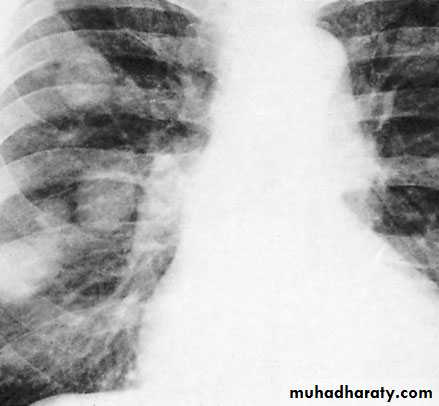

CXR: pulmonary metastases especially in teratoma